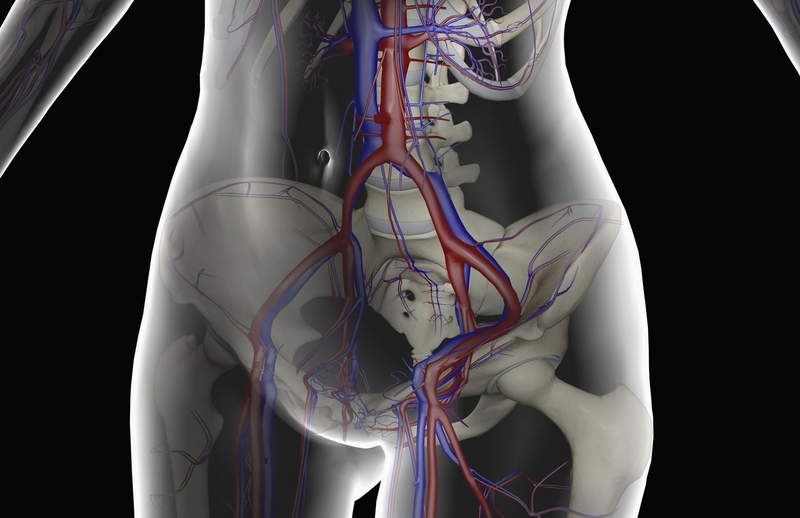

Động mạch đùi chịu trách nhiệm cung cấp máu chính cho các chi dưới. Các tĩnh mạch mũ đùi giữa là nguồn cung cấp máu cho chỏm xương đùi, động mạch vòng bên và động mạch thắt lưng. Các tĩnh mạch mũ đùi giữa là các nhánh của động mạch đùi, trong khi động mạch thắt lưng là một nhánh của động mạch chậu trong. Động mạch đùi bắt đầu từ động mạch bịt, chạy qua dây chằng chéo sau xương đùi như một nguồn cung cấp máu hỗ trợ cho chỏm xương đùi. Tuy nhiên, trong thời kỳ trưởng thành, động mạch này không phải là nguồn cung cấp máu chính.

Các nhánh xuyên của động mạch đùi sâu cung cấp máu cho trục và phần đầu xa của xương đùi.